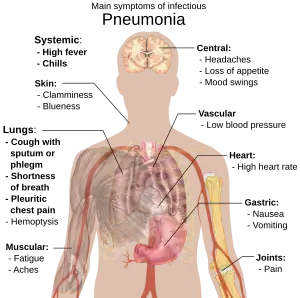

A diagram of the human body outlining the key symptoms of pneumonia

Main symptoms of infectious pneumonia

People with infectious pneumonia often have a productive cough, fever accompanied by shaking chills, shortness of breath, sharp or stabbing chest pain during deep breaths, and an increased rate of breathing.[9] In elderly people, confusion may be the most prominent sign.[9]

The typical signs and symptoms in children under five are fever, cough, and fast or difficult breathing.[20] Fever is not very specific, as it occurs in many other common illnesses and may be absent in those with severe disease, malnutrition or in the elderly. In addition, a cough is frequently absent in children less than 2 months old.[20] More severe signs and symptoms in children may include blue-tinged skin, unwillingness to drink, convulsions, ongoing vomiting, extremes of temperature, or a decreased level of consciousness.[20][21]